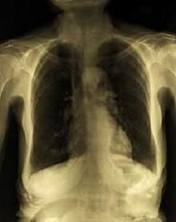

Trained physicians can perform a number of tests to diagnose bullous emphysema. A patient may be asked to blow into a spirometer to measure lung capacity or wear an oximeter on his or her finger to calculate oxygen levels in the blood. A doctor may also take x-rays or computerized tomography scans to check for the presence of enlarged and damaged air sacs. Once emphysema is determined to be the cause of a patient’s symptoms, the physician can design an individualized treatment plan.